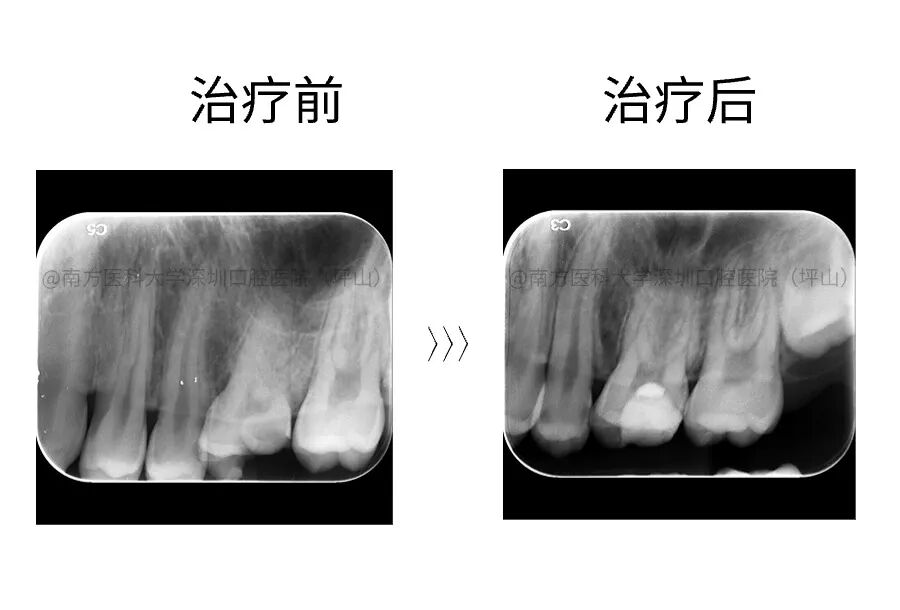

案例一

12 岁,患者左上后牙冷热酸痛,在外院因正畸需要治疗患牙,要求根管治疗。影像检查显示 26 牙远中邻面深龋近髓,根尖未见异常。建议试行活髓保存治疗。一年后复查无异常。